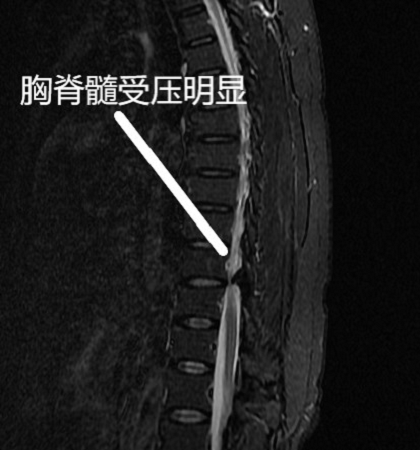

朱亮博士通过了解患者的病情,并且仔细的查体,发现患者的双下肢力量减退明显,并且膝腱反射呈亢进的状态,他认为患者目前的病情与腰椎间盘突出症不相符合,于是给予患者进一步的检查。通过核磁共振以及CT发现,患者胸椎T10/11水平黄韧带骨化,对脊髓造成了明显的压迫,是导致向女士目前症状的主要原因。

手术前的影像学检查